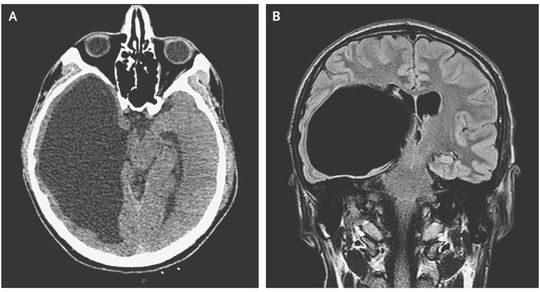

A 22-year-old man presented to the hospital after a motor vehicle collision in which his head struck the windshield of a bus. Initial observations and the physical and neurologic examinations were normal, but the injury warranted computed tomographic (CT) scanning. A CT scan of the brain (Panel A) showed an incidental finding of grossly dilated occipital and temporal horns of the right lateral ventricle. Magnetic resonance imaging (Panel B) confirmed the presence of a large cystic lesion extending from the temporal and posterior horns of the right lateral ventricle (axial size, 11 cm by 7 cm), with a mild midline shift of the third ventricle, and compression of the midbrain and brain stem with thinning of the temporal and occipital cortexes. A large, asymptomatic, intraventricular arachnoid cyst was diagnosed. Arachnoid cysts — collections of cerebrospinal fluid within the layers of the arachnoid membrane — occur infrequently. Most are congenital, but they can also be acquired after trauma or infection through the entrapment of cerebrospinal fluid within arachnoid adhesions. Neurosurgery was recommended in this case, but the patient discharged himself from the hospital and there was no further follow-up.